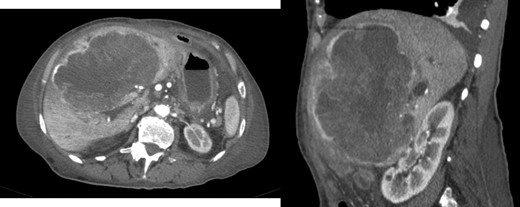

After 11 months of follow-up, the patient was admitted to the emergency room due to asthenia, nausea, vomiting and jaundice. CT scan reveal hepatic mass with 15.2 × 13.5 × 8.8 cm (Fig. 5) causing obstructive jaundice by compression of hepatic hilum.

Exploratory laparotomy was performed and non-resectability diagnosed intra-operatively. Biopsy confirmed recurrence of the disease.